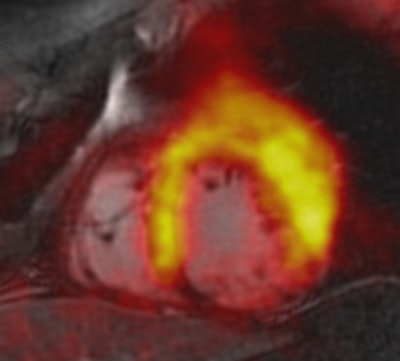

PET/MRI of patient with acute myocardial infarction due to occlusion of the right coronary artery (RCA). The fusion shows that decreased tracer uptake (within the perfusion territory of the RCA) exceeds the area of late gadolinium enhancement. The decreased tracer uptake might delineate the area at risk. Image courtesy of Dr. Felix Nensa.To better evaluate the quantitative imaging results, Nensa and colleagues developed in-house software to generate coregistered images, which compared late gadolinium-enhanced images with results from FDG-PET. Using the software in a separate group of 15 patients with visually conclusive agreement between PET and late gadolinium enhancement results, the researchers found PET defect size (35 mL) to be significantly larger than the late gadolinium-enhanced defect size (27 mL).